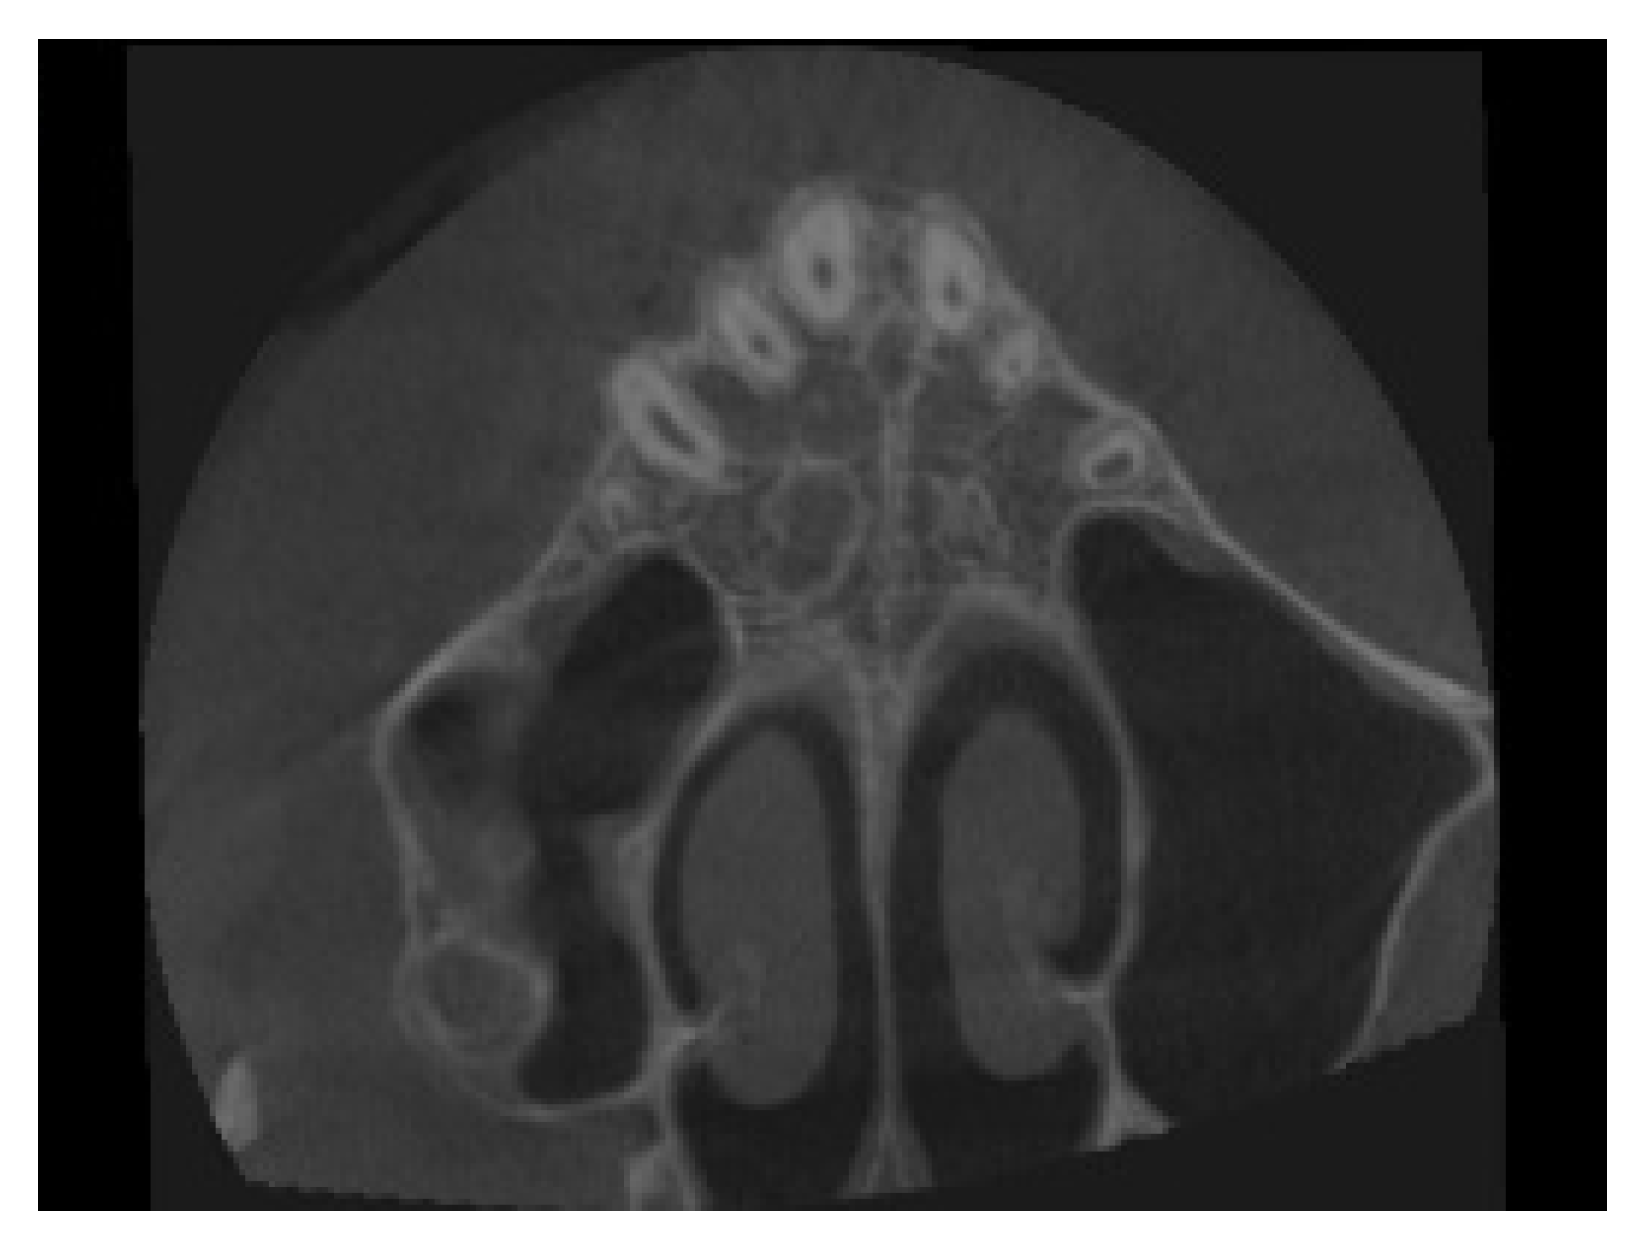

4.3. Treatment Strategy

4.4. Treatment Progress